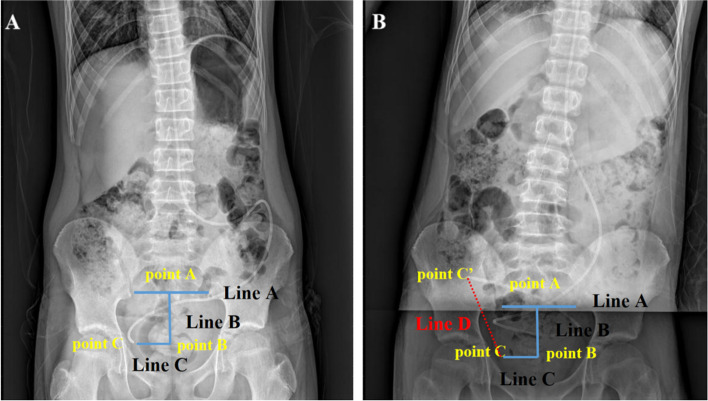

Methods: A total of 30 patients with high suspicion of DSI due to abdominal adhesions after VP surgery were included. DPAR was used for prospective assessment. The interval between the first and second PAR was 4-6 h before surgery. If two plain abdominal radiography at different times indicated that the end of the shunt tube in the abdominal segment was fixed, it was diagnosed as DSI due to adhesion of the shunt tube at the abdominal end. The peritoneal end of the shunt tube was surgically repositioned. Postoperative DPAR was repeated to evaluate the distance of the shunt outlet within the abdominal segment.

Results: All cases showed clinical symptoms or imaging findings of shunt insufficiency. The diagnostic accuracy of DPAR was 96.67% (29/30). The end of the shunt tube in the abdominal segment of the preoperative group was fixed with abdominal plain film twice with a mean difference of 1.74 ± 1.18 cm. The mean postoperative change in the position of the end of the shunt tube in the abdominal section was 9.36 ± 2.64 cm, showing a significant difference compared with the preoperative group (P < 0.001). The mean postoperative EVANs index (0.37 ± 0.08) was significantly lower than the preoperative (0.42 ± 0.08) (P = 0.007), Glasgow coma scale score (12.8 ± 2.69) was higher than the mean preoperative score (11.36 ± 2.43) (P = 0.013).